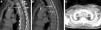

This was a 57-year-old woman with a personal history of breast cancer, with a Port-a-Cath reservoir implanted in the left pre-pectoral region. A chest computed tomography (CT) conducted for follow-up of her oncological disease with intravenous contrast medium administered via the left arm showed sclerotic lesions in several upper dorsal vertebrae, suggestive of bone metastases (Fig. 1A, B). The CT also revealed chronic thrombosis of the innominate vein carrying the port and collateral venous circulation that had developed in the anterior chest wall (Fig. 1C) and in the posterosuperior mediastium. Given the lack of chest pain, the chest CT was repeated without intravenous contrast, and the vertebral lesions seen in the previous study were not detected (nor were they seen in a dorsal spine magnetic resonance imaging (MRI) study performed a few weeks later), so the presence of vertebral bone lesions could be ruled out.

(A) Sagittal reconstruction of the chest CT with intravenous contrast medium showing focal sclerotic bone lesions in the posterior margin of the T2 and T3 vertebral bodies, mimicking vertebral metastases. Note the port catheter in the theoretical position of the thrombosed innominate vein (short vertical arrow) and the development of collateral venous circulation in the perivertebral veins (short horizontal arrows). (B) Sagittal reconstruction of the chest CT with intravenous contrast medium showing focal sclerotic bone lesions in the posterior margin of the T3 and T5 vertebral bodies (long arrows). Note the port catheter in the theoretical position of the thrombosed innominate vein (short arrow). (C) Maximum intensity projection axial reconstruction of CT, showing development of collateral venous circulation in the anterior chest wall (arrows).